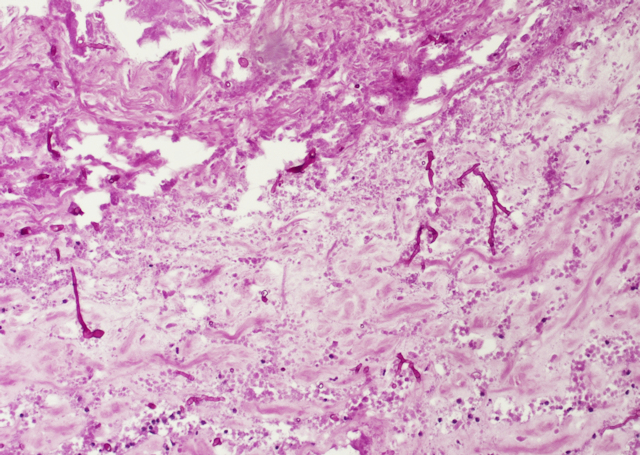

In der feingeweblichen Untersuchung wurde festgestellt, dass es sich bei den herdförmigen Veränderungen in der Wand des Pansens um Infarkte handelte, in denen zahlreiche Schimmelpilzhyphen nachgewiesen werden konnten (Bild 4 und 5).

Bild 5: Nachweis der Schimmelpilzhyphen mittels Spezialfärbung, PAS-Reaktion, 100fache Vergrößerung

Die Hyphen stellten sich als relativ breit (5-20 µm), wenig septiert, mit rechtwinkligen, 45° und dichotomen Verzweigungen dar und waren stark fragmentiert. Eine sichere Unterscheidung zwischen Mucorales und Aspergillus spp. war mittels feingeweblicher Untersuchung nicht möglich. Aufgrund der wenig bis nicht septierten Hyphen und der Affinität zu Blutgefäßen mit Thrombusbildung wurde der Verdacht auf eine Infektion mit Mucorales erhoben.